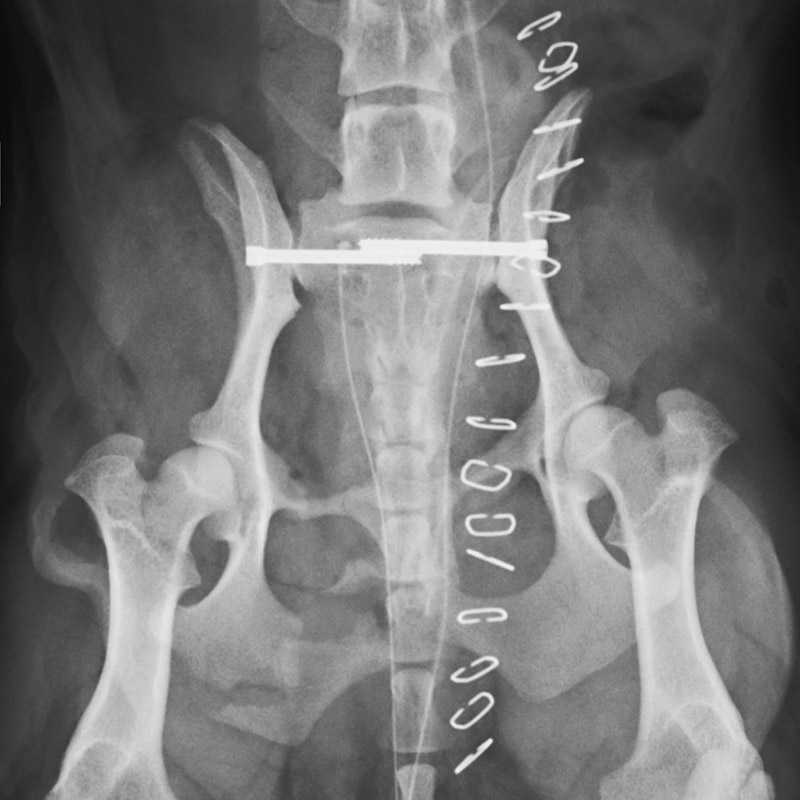

骨盤骨折

猫(2歳)

交通事故

手術前

手術後